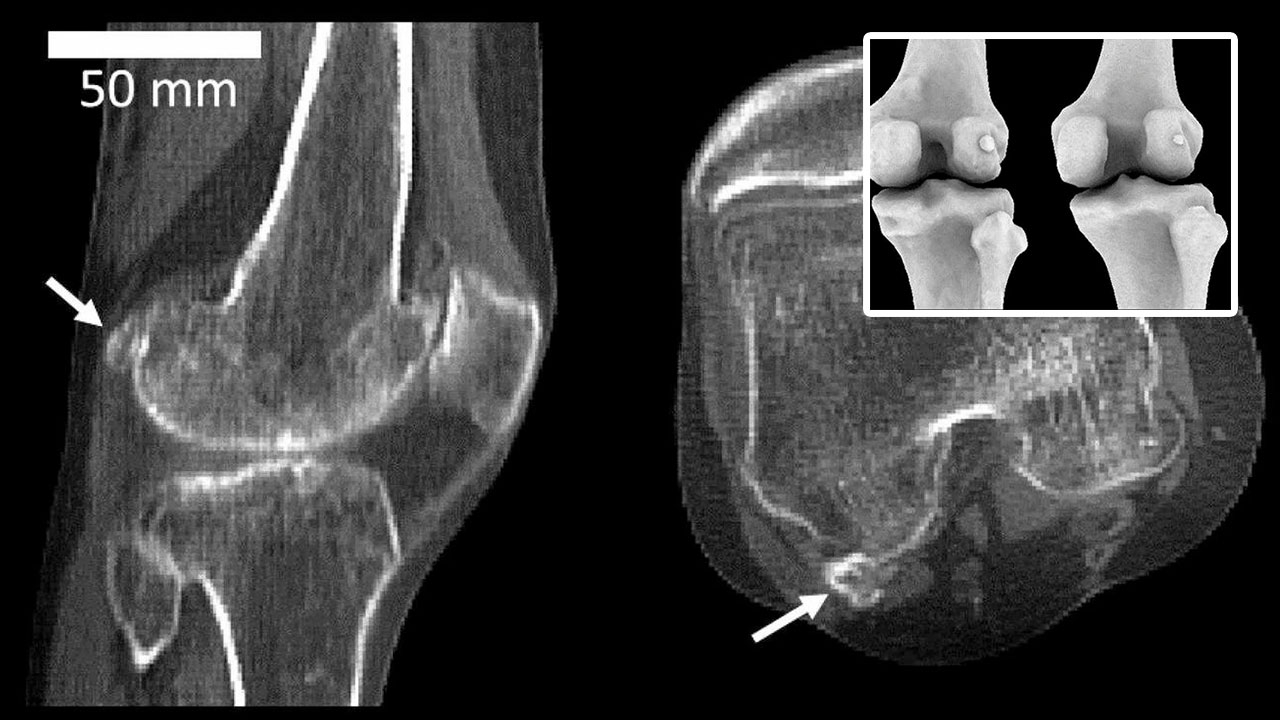

ล่าสุดนักวิทยาศาสตร์จากอิมพีเรียล คอลเลจ ลอนดอน ในประเทศอังกฤษ เผยว่า ค้นพบกระดูกฟาเบลลาอีกครั้งในร่างกายมนุษย์ และดูจะเป็นการกลับมาอย่างลึกลับในช่วงกว่า 100 ปีที่ผ่านมา พวกเขาอธิบายว่าฟาเบลลาเป็นกระดูกเล็กๆ ที่ฝังอยู่ในเอ็นหลังหัวเข่า และไม่มีหน้าที่การทำงานที่ชัดเจน แต่กลับทำให้เกิดความเจ็บปวดสำหรับบางคนจนอาจต้องถอนออกหากกระดูกชิ้นนี้ก่อเกิดปัญหา

นักวิทยาศาสตร์เผยว่าในปี พ.ศ.2461 มีการค้นพบว่า ประชากรของโลก 11.2% มีกระดูกฟาเบลลา แต่ทุกวันนี้เพิ่มขึ้น 3.5 เท่า หรือคิดเป็น 39% ซึ่งนักวิทยาศาสตร์เผยว่า การปรากฏตัวของกระดูกฟาเบลลาอาจรบกวนการทำงานของข้อต่อ และอาจเชื่อมโยงกับโรคข้อเข่าเสื่อมนั่นเอง.